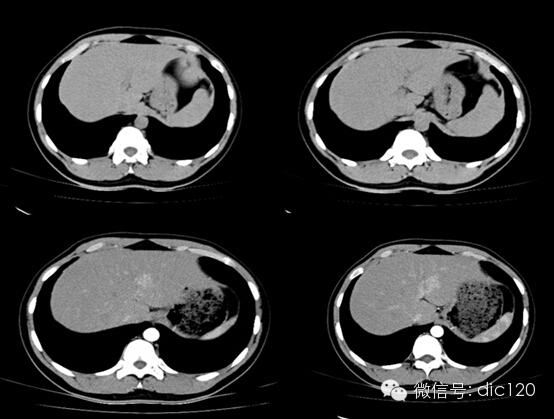

• 肝局灶性結節增生(FNH)

肝局灶性結節增生(FNH)

男,21Y,門診患者,病史不詳影像表現:CT平掃與正常肝組織呈等密度,密度均勻,動脈期病灶快速明顯均勻強化,中心見小片狀低密度影(瘢痕),門脈期及延遲期對比劑快速退出呈等密度,中央低密度影延遲強化。MRI腫塊T2WI為稍高信號,中央高信號。動態增強掃描動脈期均顯著增強,門脈期輕度增強,延遲期瘢痕強化。

隨訪外院手術病理:肝FNH。

鑒別診斷:1、肝血管瘤:增